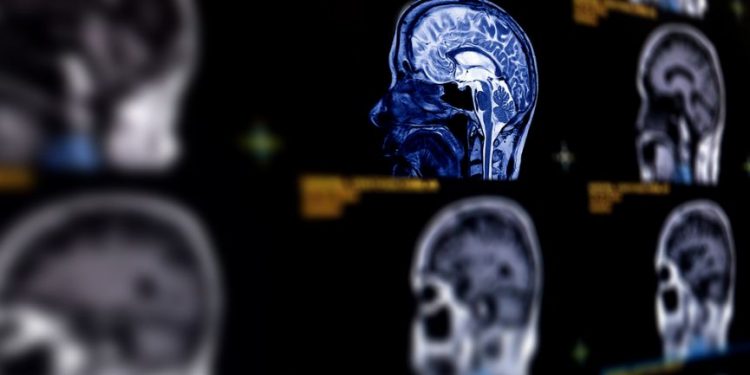

Identifying the tumor is the first step. To do this, a neurological exam and imaging tests are typically performed. An MRI scan can determine the exact location of the tumor. For more detailed information, a patient may have a biopsy of the tumor.